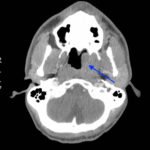

The photograph demonstrates an area of ulcerative tissue at the left palatine tonsil without surrounding erythema or purulent drainage. The computed tomography (CT) scan shows a large ulceration of the left soft palate and palatine tonsil (red arrow). There is no evidence of skull base osteomyelitis. There is suppurative lymphadenopathy with partial left jugular vein compression due to mass effect (yellow highlight). There is mild nasopharyngeal airway narrowing with architectural distortion (blue arrow), but no other evidence of airway obstruction.